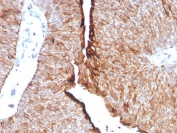

IHC staining of FFPE human bladder carcinoma tissue with recombinant Uroplakin 1B antibody (clone UPK1B/9258R). Inset: PBS used in place of primary Ab (secondary Ab negative control). HIER: boil tissue sections in pH 9 10mM Tris with 1mM EDTA for 20 min and allow to cool before testing.

IHC staining of FFPE human bladder carcinoma tissue with recombinant Uroplakin 1B antibody (clone UPK1B/9258R). HIER: boil tissue sections in pH 9 10mM Tris with 1mM EDTA for 20 min and allow to cool before testing.